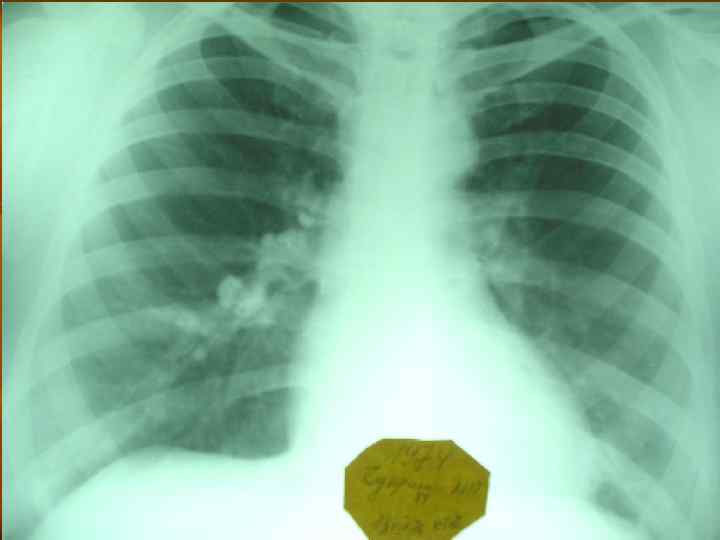

Первичный туберкулезный комплекс (пневмоническая стадия) n Рентгенологическая картина: определяется инфильтрат «идущий» от периферии к корню легкого.

Первичный туберкулезный комплекс (стадия рассасывания) n Рентгенологическая картина: определяется фокусная тень связанная дорожкой с расширенным корнем (легочный аффект + лимфангоит +лимфоаденит).

Первичный туберкулезный комплекс (стадия организации и уплотнения) n Рентгенологическая картина: определяется плотная очаговая тень в легком и в корне не связанные между собой.

Первичный туберкулезный комплекс (стадия петрификации) n n Вариант клинического излечения Рентгенологически определяется петрификат в легком (очаг Гона) и в корне.

Первичный туберкулезный комплекс